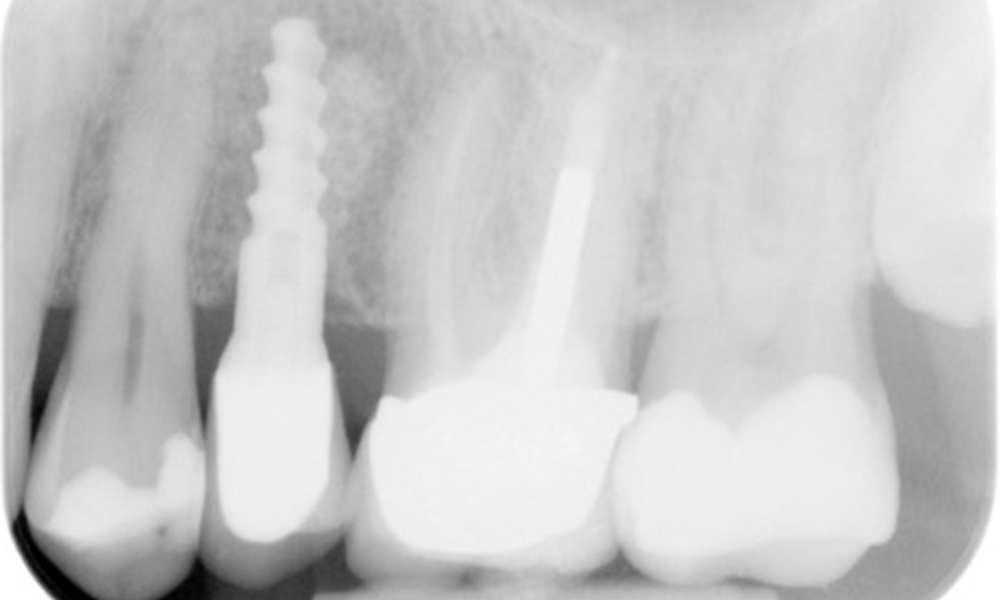

Der Patient hat einige zahnärztliche Restaurationen und zwei Implantate (2. und 4. Quadrant). Anhand der aktuellen Befunde lässt sich eine Gingivitis bei stabilem parodontalen Zustand am reduzierten Parodont (Stadium III, Grad A) feststellen.

Versorgungen: zahnärztliche Restaurationen (NEM keramisch verblendet), zwei Implantate (2., 4. Quadrant)

Der Patient zeigt keine besonderen Risikofaktoren mit spezifischen zahnmedizinischen Auswirkungen. Daher ist der aus der Mundgesundheit ermittelte Bedarf maßgebend. Hierbei zeigt sich eine gute Mundgesundheit mit stabilem, reduzierten Parodont. Sollte sich bei einem Kontrolltermin am Implantat eine Vergrößerung von ST im Vergleich zur Baseline kombiniert mit einer diffusen Blutung zeigen, so sollte eine Röntgendiagnostik (i. S. eines Zahnfilms) erfolgen, um frühzeitig einen periimplantären Knochenverlust zu erkennen und dagegen zu intervenieren.